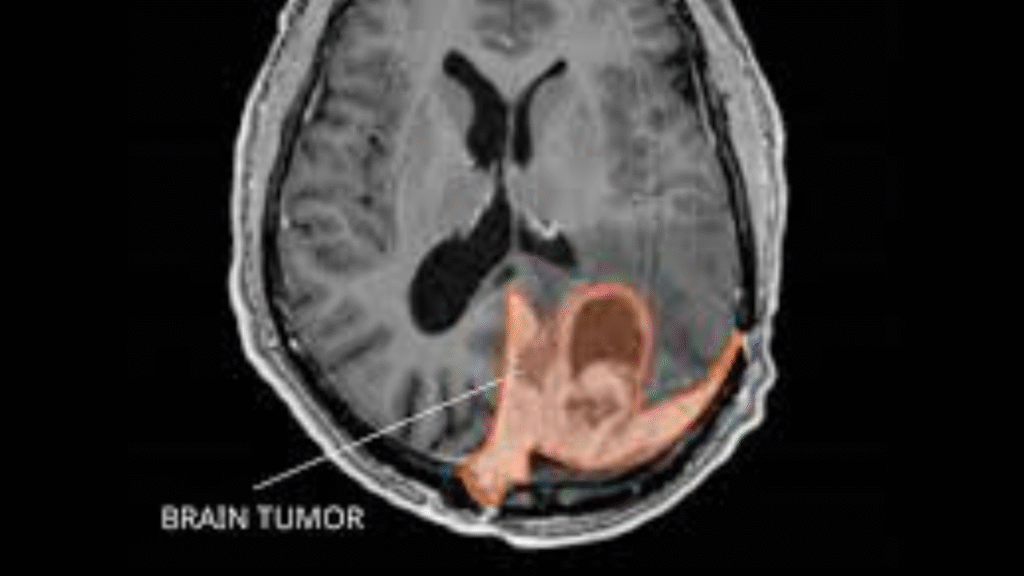

When genetic abnormalities occur in normal brain cells, brain tumours can develop. Cells proliferate and divide quickly as a result of these alterations. Tumour cells do not spontaneously perish as healthy cells do. They build up and create a lump, which may be cancerous or benign.

What is the meaning of a brain tumour in simple terms? It occurs when your brain cells begin to proliferate out of control. Your skull becomes compressed as a result, impairing regular brain activity.

How is a brain tumour formed structurally? The aberrant cells group together to form a noticeable bulk. This tumour may compress healthy brain tissue. It may also block fluid flow or affect blood supply.